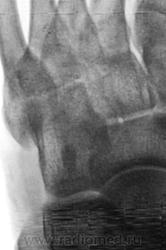

Пол пациента: Женский пол Тип патологии: Травма Область исследования: Скелетно-мышечная система Методы исследования: Rg Пациент направлен по поводу травмы. Случайная находка... https://radiomed.ru/sites/default/files/styles/case_slider_image/public/user/12/2.201310200016.jpg?itok=VzEdq3KK https://radiomed.ru/sites/default/files/styles/case_slider_image/public/user/12/3.201201010012_2.jpg?itok=US4gX77V https://radiomed.ru/sites/default/files/styles/case_slider_image/public/user/12/4.201310200014.jpg?itok=l6zzwcyf ID:32564 Пнд, 21/10/2013 - 23:57 #1 И.Бондаренко Не на сайте Был на сайте: 4 дня 2 часа назад Зарегистрирован: 13.09.2011 - 22:55 Публикации: 9206 И что это? Такое встречается, описываю как участок склероза или внимания не обращаю. Втр, 22/10/2013 - 16:54 #2 Pilulia Не на сайте Был на сайте: 7 лет 9 месяцев назад Зарегистрирован: 02.09.2011 - 14:27 Публикации: 14 или добавочная сесамовидная кость, как вариант.. Втр, 22/10/2013 - 22:16 #3 Катенёв Валенти... Не на сайте Был на сайте: 7 лет 2 недели назад Зарегистрирован: 22.03.2008 - 22:15 Публикации: 54876 Pilulia wrote: или добавочная сесамовидная кость, как вариант.. Добавочная? Сесамовидная?

И что это? Такое встречается, описываю как участок склероза или внимания не обращаю.

или добавочная сесамовидная кость, как вариант..

Добавочная?

Сесамовидная?